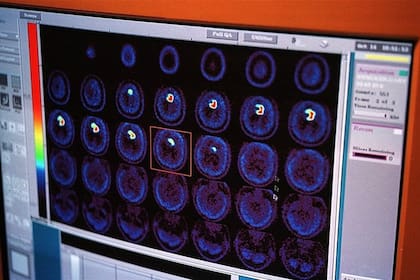

El estudio se basó en tomografías cerebrales de casi 40.000 adultos de entre 44 y 82 años que residen en Reino Unido.

Los investigadores estudiaron los factores de riesgo genéticos y los modificables que aumentan la vulnerabilidad “de las partes más frágiles del cerebro” mediante el estudio de tomografías cerebrales de casi 40.000 personas relativamente sanas que extrajeron del Biobanco del Reino Unido.